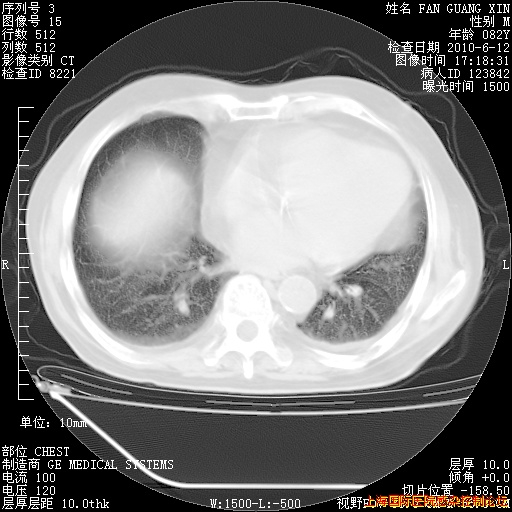

补发6月12日肺部CT肺窗

6月12日肺窗

整整相隔30天的肺部CT好像有所好转啊。甲强龙减量第3天,需要观察体温。